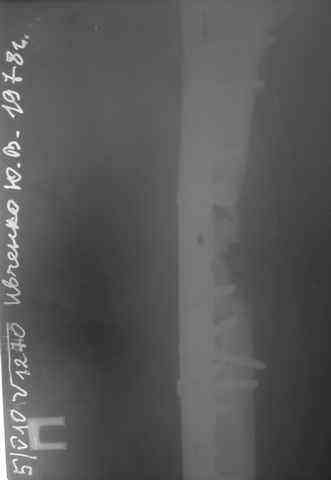

Несрошийся открытый фрагментарный,оскольчатый,перелом в/с/3 правого бедра |

Несрошийся открытый фрагментарный, оскольчатый, перелом в/с/3 правого бедра с размозжением мягких тканей. Состояние после ПХО,МОС,ВО ЧКФ стержневым АВФ. 10.10.09.Заживление раны per prima. Операция:16.12.09,открытый накостный МОС,аутокостная пластика(из крыла подвздошной кости)правого бедра. После п/о периоде заживление раны вторичным натяжением (на 5-е сутки распущены швы, после очищения раны наложины вторичные швы) На этапных RO-гр:остеолизис костного трансплантата и дистального фрагмента перелома бедра. Вопрос:дальнейшая тактика лечения-БИОС аутокостная пластика (трансплантат на сосудистой ножке М/Б кости). Билокальный остеосинтез по Илизарову с остеотомией подвертельной и надмыщелковой области бедра. Мозможен ли аутотрансплантат без сосудистой ножки? Чем улучшить васкуляризацию? Декортикация? Тактика выжидания остеолизиса, а затем оперативное лечение.